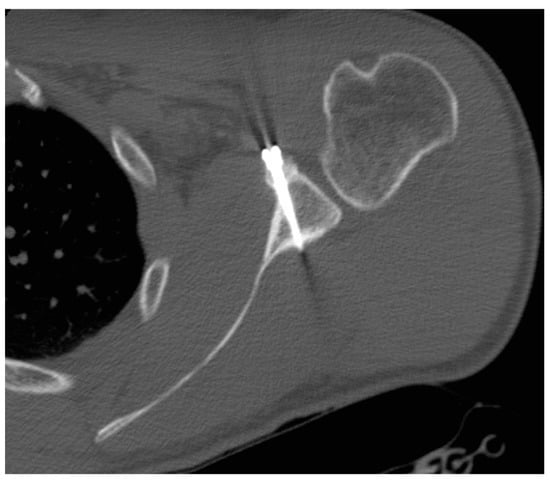

- The pectoralis minor was released, and a fresh portal was established with a needle over the coracoid, to insert the drill holes, at the junction of the lateral 2/3 and the medial 1/3. Two Kirschner wires through the coracoid were passed. The drill guide was removed. The holes were tapped, and the top hats were inserted into the fragment using a flexible Chia wire. The osteotomy was completed (Figure 2). The bone fragment was secured thought a coracoid screw passed over the Chia wire, using a double cannula.